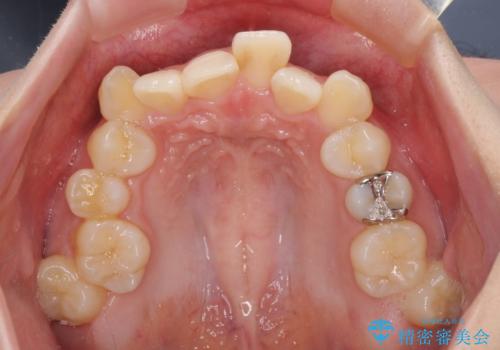

- 前歯の叢生と八重歯を気にして来院された患者様です。

叢生が強く、奥歯の咬合も左右差が大きかったため、上下左右4本を抜歯して、ワイヤー矯正を行うこととしました。

20歳前後と年齢が若かったため、非常にスムーズに歯列が整い、1年半をかけずに治療を終えることができました。